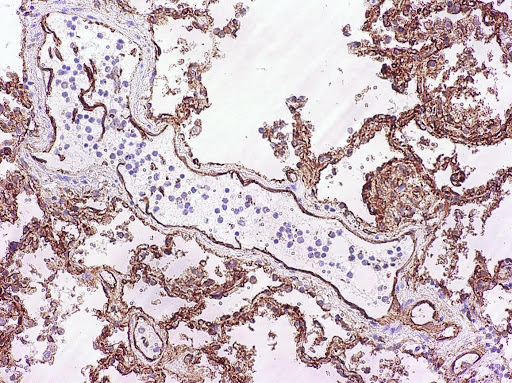

Image: CD54+ (ICAM-1) positive endothelial cells in a lung vessel. Of note, the epithelial positive staining is typical and can act as internal control. (Image credit: Sebastian Lucas).